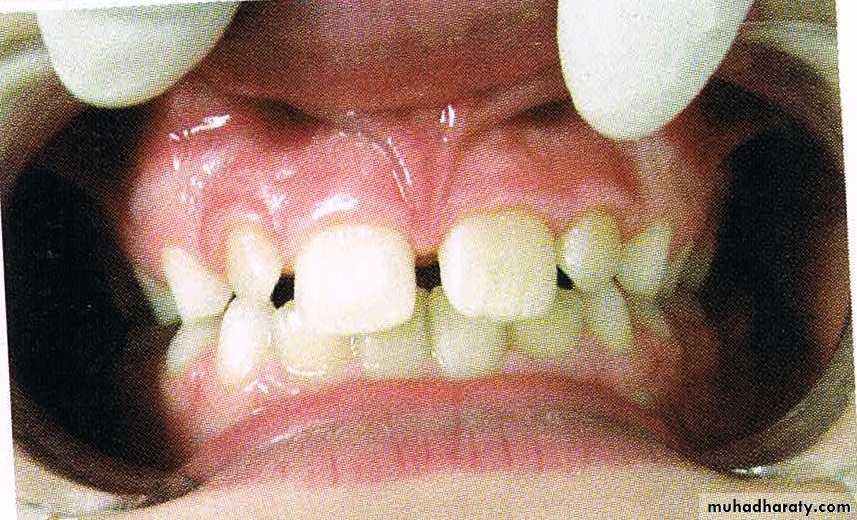

50a) Physiologic median diastema/ ugly duckling stage

It is a transient or self correcting malocclusion which is seen in the maxillary incisor region between 8-9 years. It is particularly seen during the eruption of the permanent canines.

51